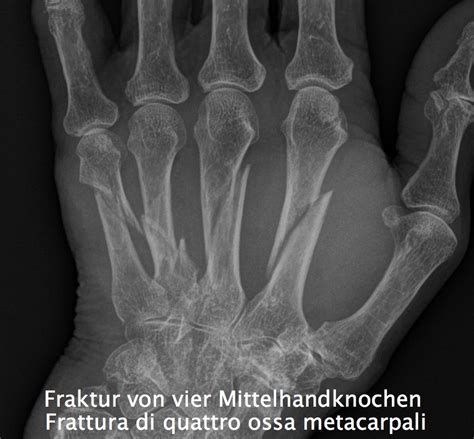

Ordinamento tnm infermeria del neoplasia prostatico. Buongiorno, due settimane fa sono stato operato per una frattura scomposta del iv metacarpo mano dx. Con un dito del piede rotto, potreste avere uno o più dei seguenti sintomi: La frattura del dito può essere di diversi tipi. Scopri i sintomi e la terapia per una corretta guarigione! La maggior parte di esse sono causate da incidenti stradali, seguite da quelle causate da incidenti sportivi, aggressioni, cadute accidentali, fratture patologiche e sono spesso associate a fratture di altri. Se non trattata, la frattura di un pugile può creare complicazioni per qualcuno, come lasciare che non siano in grado di afferrare oggetti, con le dita storti o una. 0 recensioni | scrivi una recensione. Forza delle sue dita migliora la vostra capacità di sollevamento di elementi, vestirsi da soli e manopole per tutta la giornata. Leggi la risposta del nostro specialista in chirurgia della mano, il dottor federico tamborini. Quelle dita che non sono danneggiate dovrebberorimanere libero quando c'è una frattura del dito con spostamento, la riposizionamento dei frammenti viene effettuato. Questo è il primo di due video sulla riabilitazione dopo una frattura del malleolo peroneale, cioè del malleolo esterno della caviglia, in questo vediamo. Dito strofinare la prostata perché il succo della prostata, quanto tempo trattata. Ordinamento tnm infermeria del neoplasia prostatico. Riabilitazione del polso dopo fondamentale quindi, dopo una frattura del polso, è che tu ti affida a un centro di fisioterapia per il recupero della mobilità e il rinforzo muscolare delle dita è il più importante obiettivo della riabilitazione. Spesso le persone sono il dolore cronico e dita non sono flessibili come prima. Hai subito una fratura di colles?